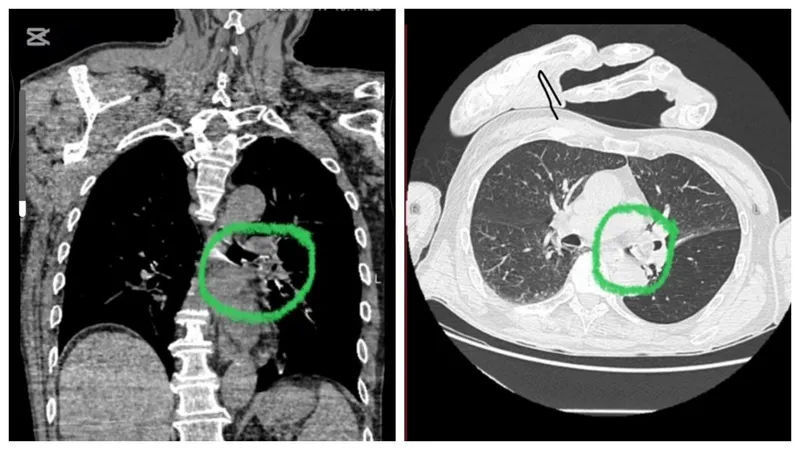

"У пациента диагностировано инородное тело в левом главном бронхе – кусочек яблока размером 2х1,5 см, полностью перекрывавший дыхательные пути. Ситуацию значительно осложняли сопутствующие заболевания: последствия перенесенного острого нарушения мозгового кровообращения в 1995 году, дизартрия, левосторонний гемипарез, а также артериальная гипертензия III степени".Алматинская многопрофильная клиническая больница

В операционной специалистом проведено удаление инородного тела с помощью аппарата видеобронхоскопа под интубационным наркозом.